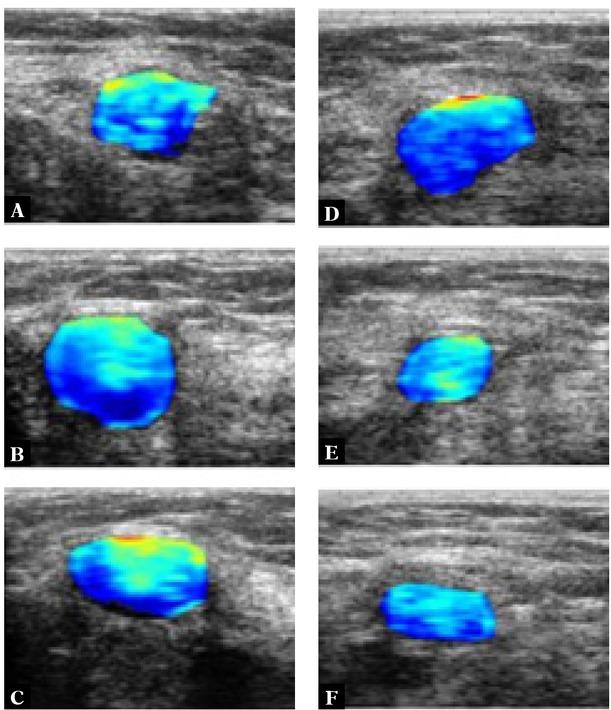

Fig. 2